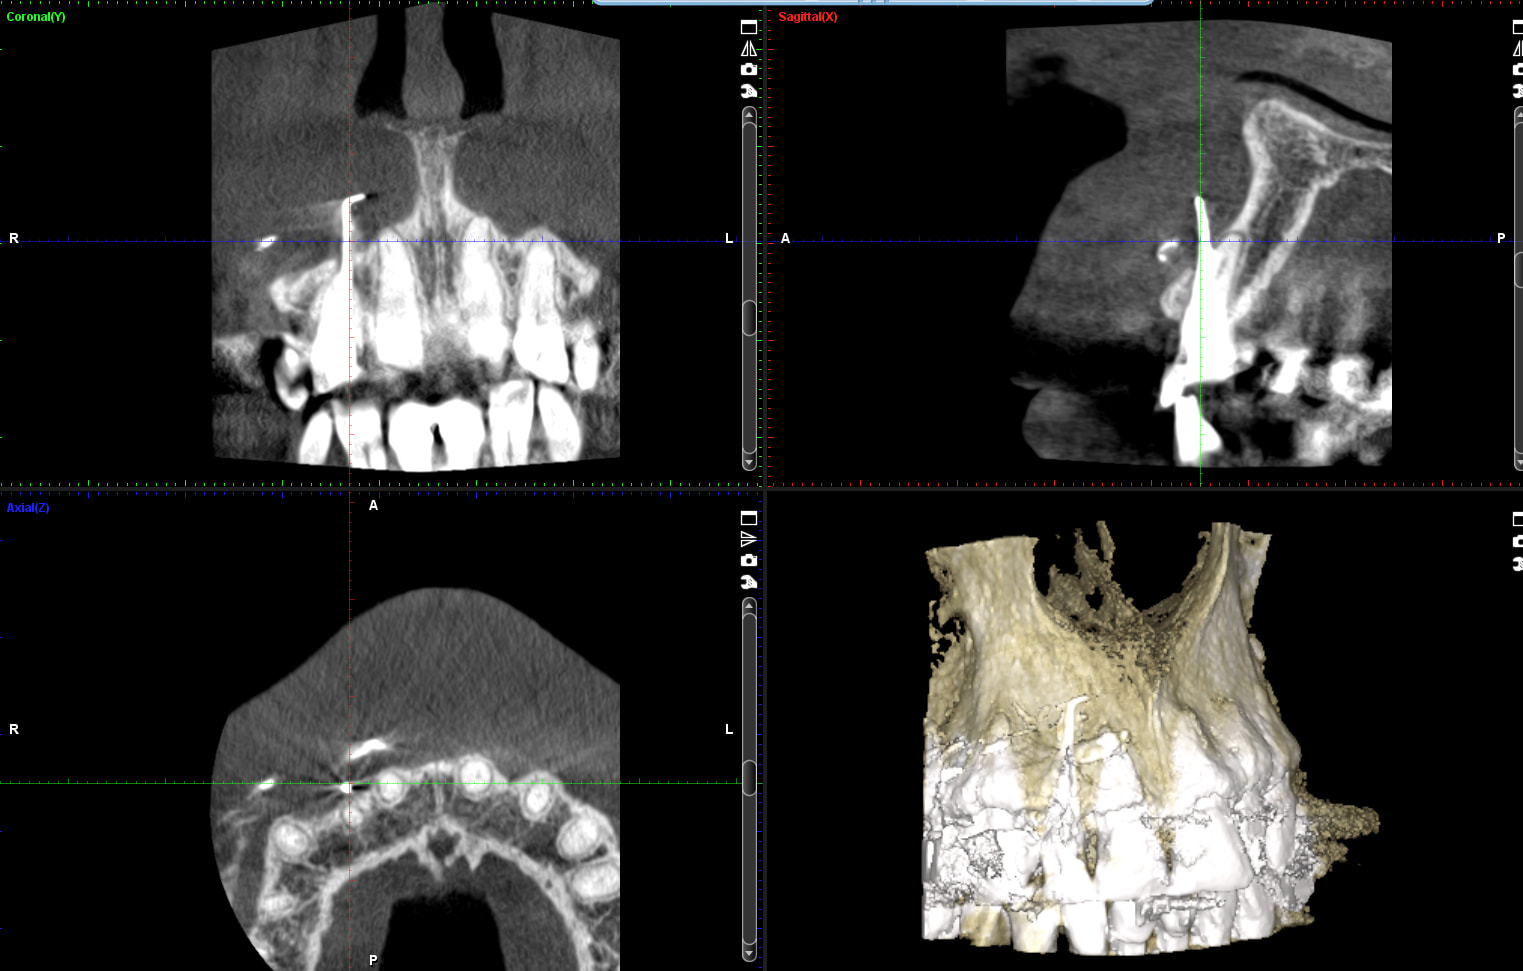

franchement ton truc va vite faire pschitt, ben oui faux canal , léger emphysème lié à l'hypochlorite, après c'est certain ça a été géré (même par quelqu'un d'autre ça a été géré) donc pas de perte de chance à priori , juste douleur mais quantifiable ? tu t'es déjà expliqué avec le patient qui en veut peut être plus tu verras bien ... tiens pour te dire que parfois ça peut aller plus loin je te mets une petite photo d'un cas "extrême" dent mise en attente de cicatrisation après deux injection d'hypochlorite en deux séances une sous al et une sans "pour voir" ... la indemnisation il y a eu